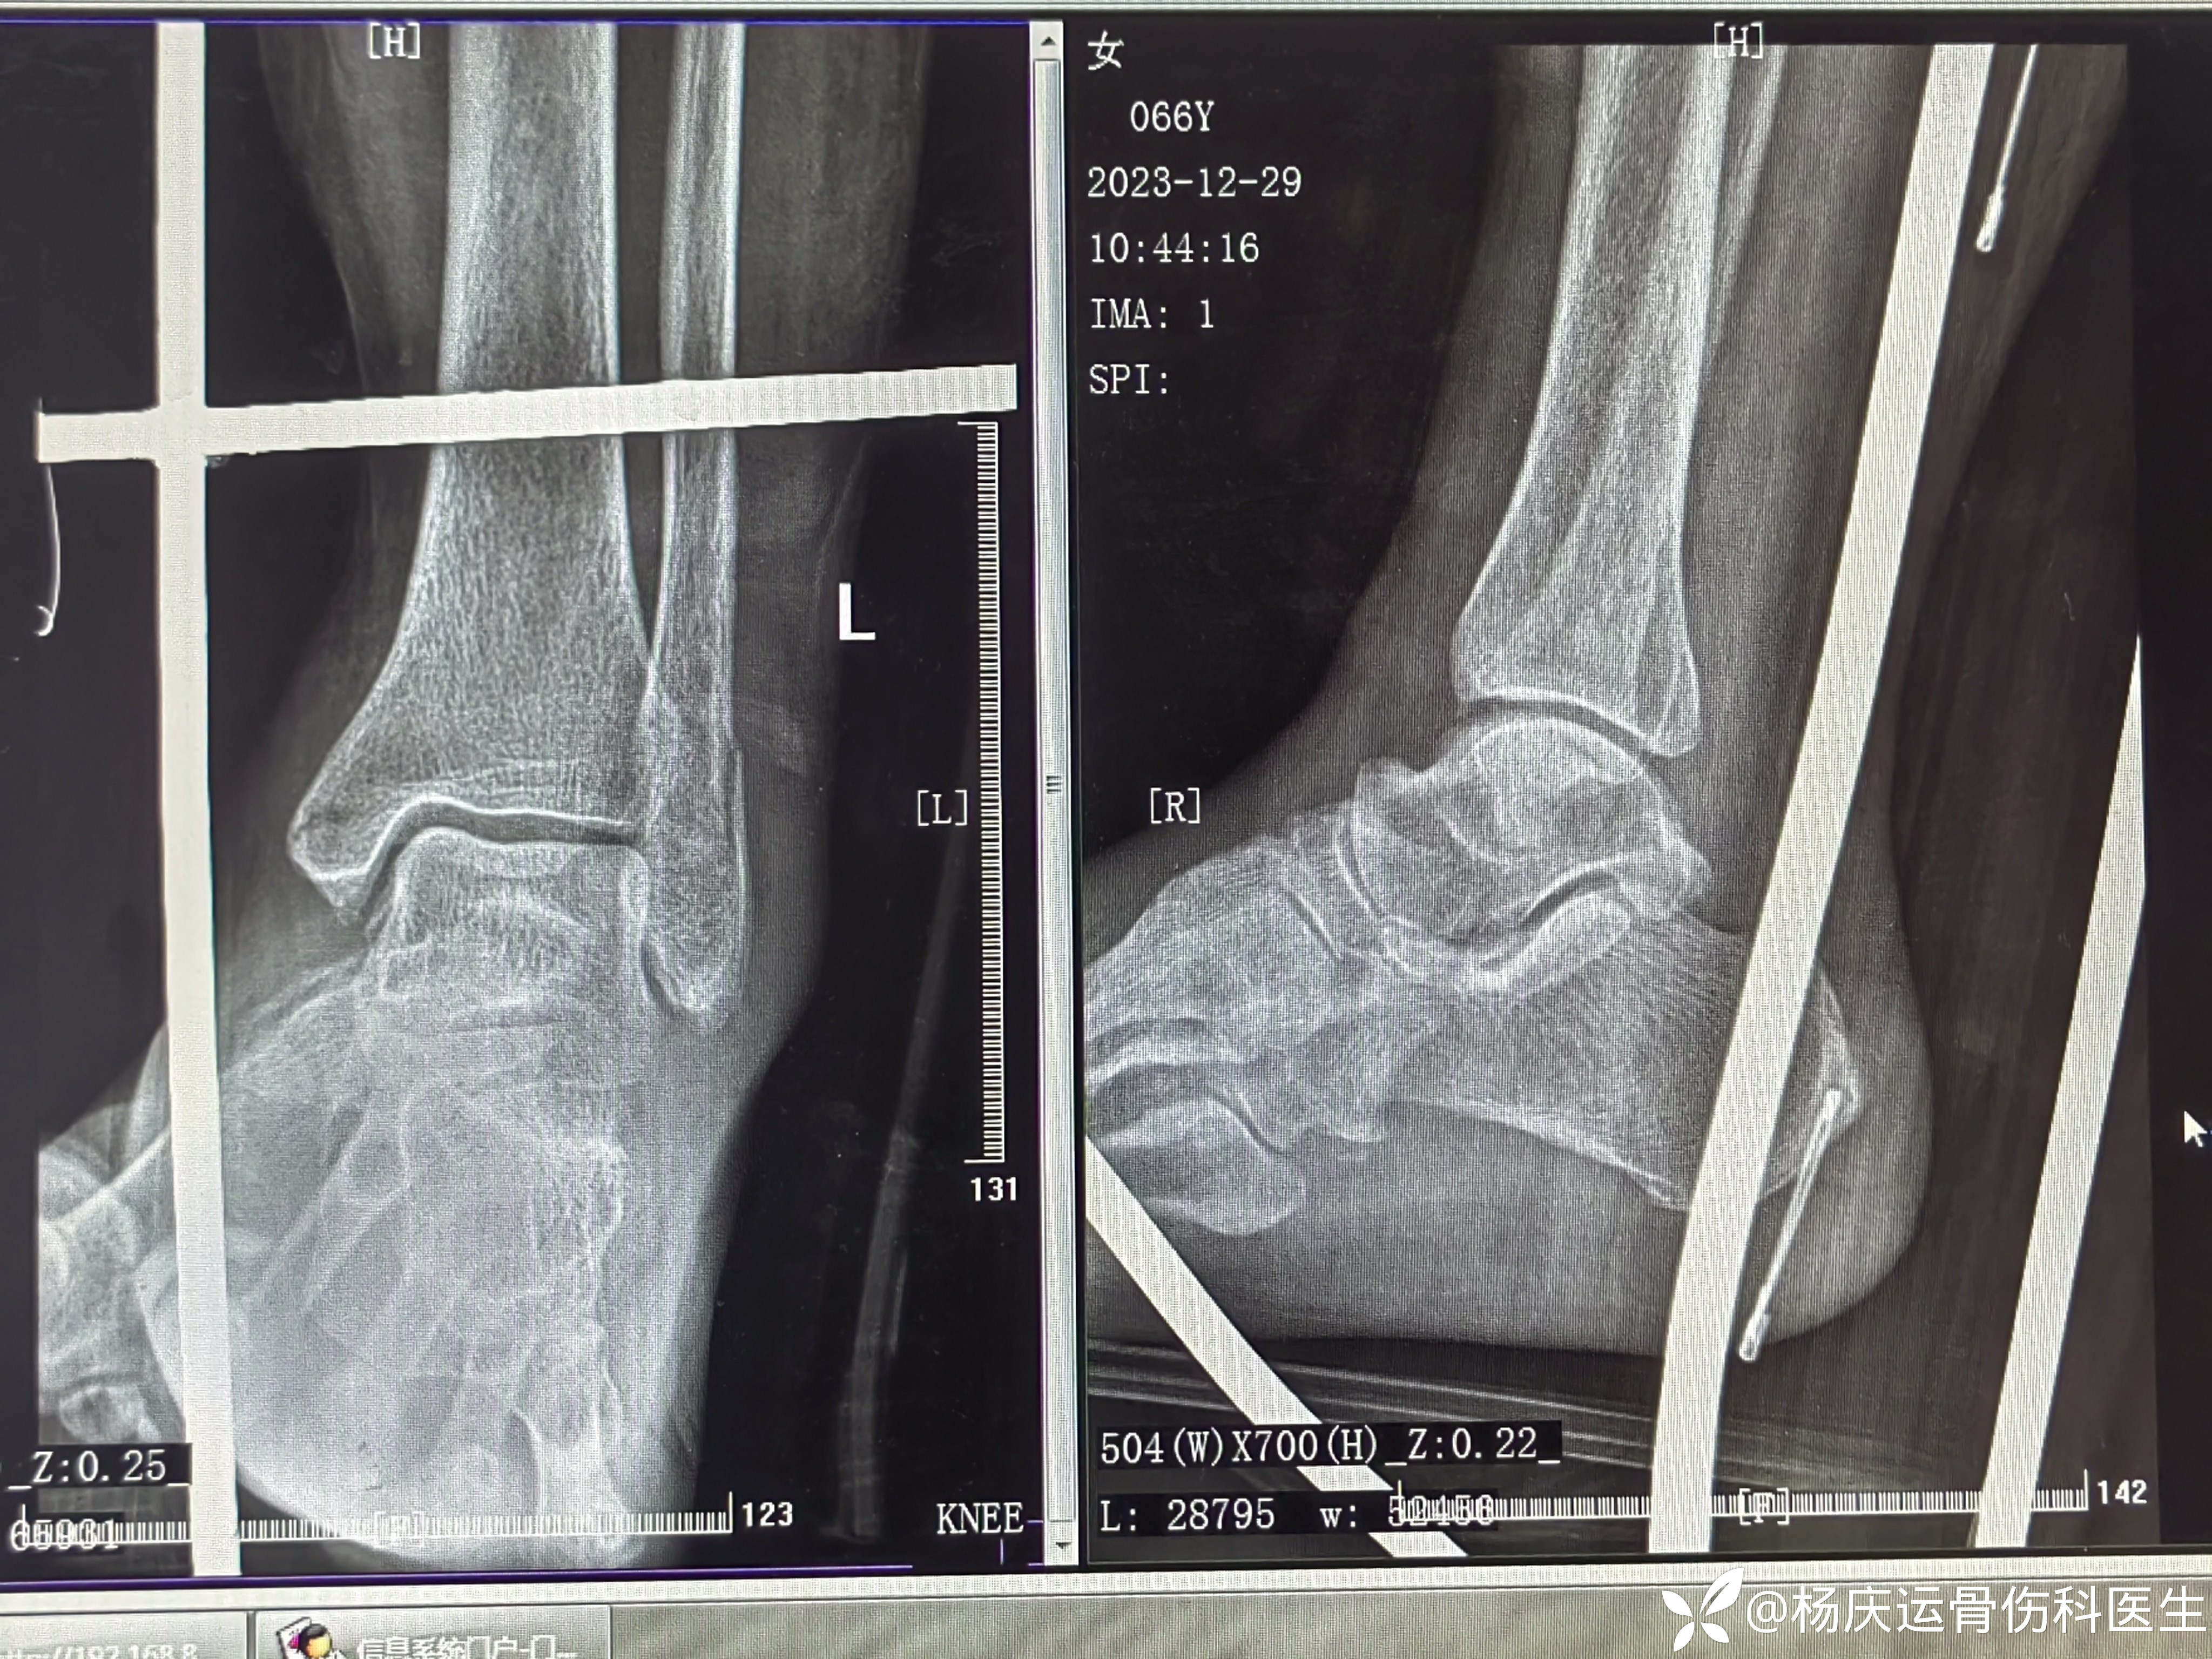

患者矫,女,66岁,左踝扭伤肿痛畸形2小时

初步诊断:左踝关节骨折(L-H分型:旋后外旋型IV)

首诊片